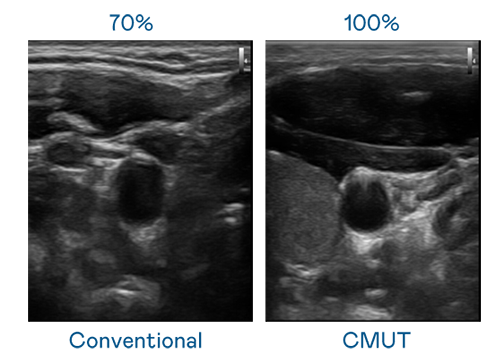

CMUT 技術是一種用電容式微機電元件來產生超音波訊號的技術。與傳統 PZT 壓電式技術相比,CMUT 頻寬增加 30%,更寬頻的超音波訊號讓影像解析度大幅提升,是實現高影像品質醫療超音波掃描、促進精準醫療發展的關鍵技術。

超音波影像的解析度高低,首先取決於探頭能發出的訊號頻寬。大庄家 CMUT 可提供高清晰的超音波訊號,提供高頻寬、高靈敏度、影像紋理細節更高的超音波影像,協助醫護人員縮短影像判讀時間及利用精準的醫療影像進行診斷。